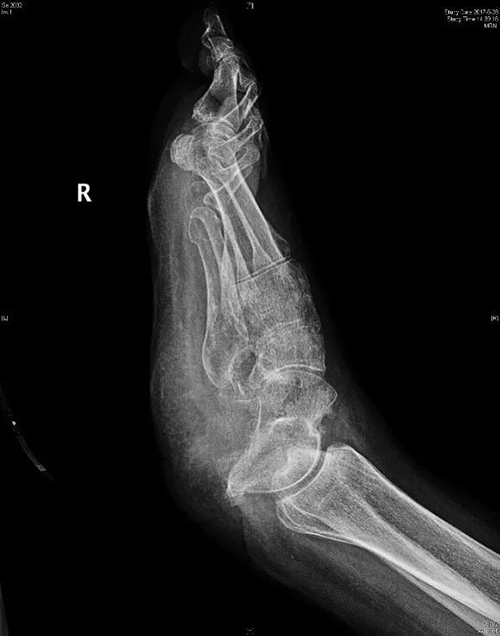

术前X线片可见跟骨完全缺失